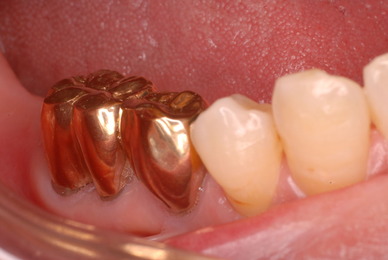

色々不満な入れ歯です。

発音や見える金属が気になるようです。